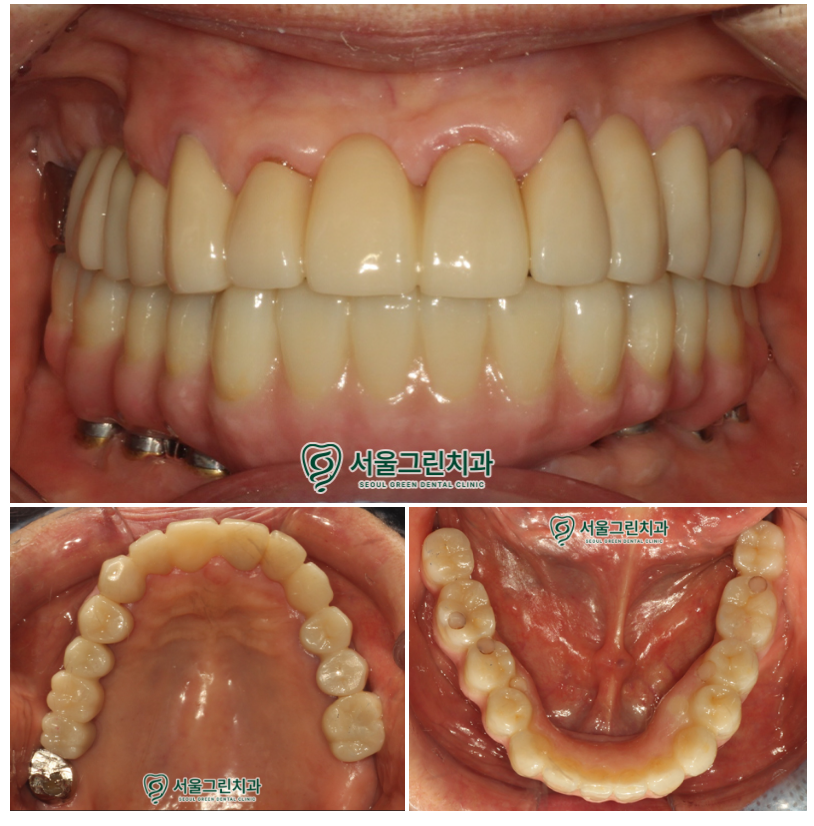

위아래 모든 치료가 마무리 된 후,

구강 내 모습입니다!

치료 후 환자분께서는

틀니를 빼고 끼는 번거로움이 사라져

매우 편해졌으며,

이전보다 훨씬 안정적으로 씹을 수 있게 되었다고

만족해하셨답니다.